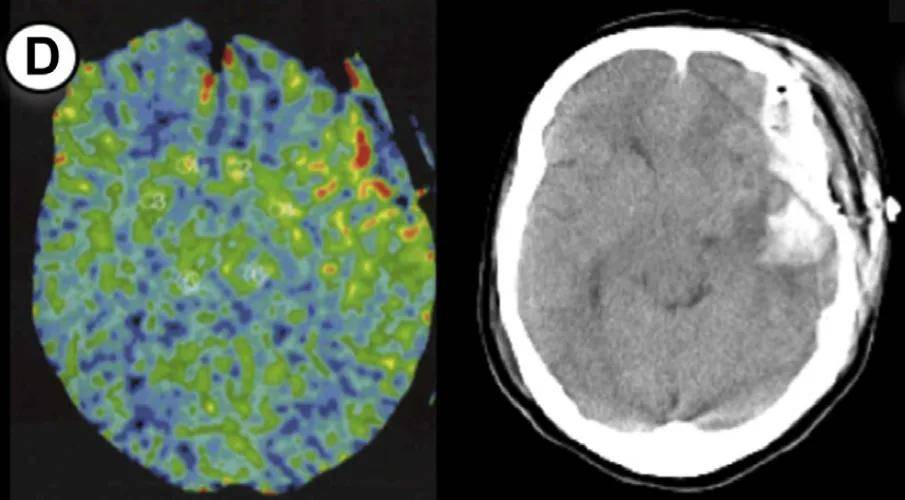

病例1:55岁男性,右侧大脑手术。方法1 rCBF增加率47%,方法2达55%(超过50%阈值)。术后第3天未维持镇静,第2天发生脑出血,改良Rankin量表评分恶化。

病例2:55岁男性,左侧大脑手术。方法1和方法2的rCBF增加率均为50%,达到预警阈值。术后第1天发现少量蛛网膜下腔出血(SAH),因术前规划2天镇静和血压控制,未出现神经功能缺损。

病例3:44岁女性,左侧大脑手术。方法1 rCBF增加率100%,方法2达114%,术后第2天脑出血。因术后及时给予1天镇静和严格控压,未遗留神经功能问题。

病例4:49岁女性,右侧大脑手术。方法1 rCBF增加率89%,方法2达133%,术后第5天发现硬膜下血肿合并蛛网膜下腔出血。

病例5:49岁男性,左侧大脑手术。方法1 rCBF增加率78%,方法2高达149%,术后第2天发现少量蛛网膜下腔出血。术后给予1天持续镇静,出血未扩大。

病例6:26岁男性,右侧大脑手术。方法1 rCBF增加率63%,方法2达72%,术后第2天发现硬膜下血肿合并蛛网膜下腔出血。术后1天镇静干预后出血吸收。

病例7:35岁女性,左侧大脑手术。方法1 rCBF增加率77%,方法2达67%,术后第2天发现出血合并脑室内出血。因术前知晓rCBF超标,提前规划镇静干预。

7个病例年龄范围25-55岁(无儿童),出血类型包括脑出血(ICH)、蛛网膜下腔出血(SAH)、硬膜下血肿(SDH)及混合出血,发病时间术后1-5天。所有患者rCBF增加率均≥30%(方法1)或≥50%(方法2),证实这两个阈值的预警价值。